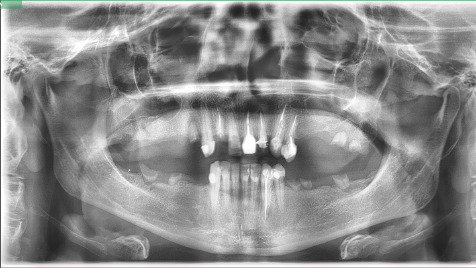

Na podstawie zdjęcia pantomograficznego uzębienia stwierdzono konieczność odbudowy 6–8 koron protetycznych. Szacunkowy koszt planowanego leczenia wynosi około 15 000 zł.